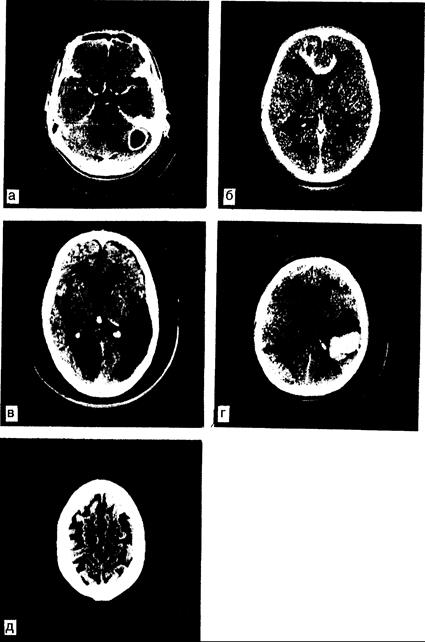

Рис. 341-1. Компьютерные томограммы при различных заболеваниях. Лобные доли расположены выше; правое полушарие находится слева от читателя. а — абсцесс левого полушария мозжечка, развившийся как осложнение инфекции сосцевидного синуса. На снимке с контрастным усилением видно типичное «кольцевидное» контрастирование; б — злокачественная астроцитома с инфильтративным прорастанием в мозолистое тело и белое вещество обеих лобных долей. Видна зона отека вокруг опухоли в лобных долях; в — массивные двусторонние инфаркты мозга: в бассейне правой задней мозговой артерии и бассейне левой средней мозговой артерии; г — внутримозговая гематома в левой теменной доле. Кровь в зоне кровоизлияния выявляется без введения контрастного вещества; д — атрофия коры головного мозга при болезни Альцгеймера.

Компьютерная томография (КТ). В ходе данной радиологической процедуры проводят компьютерную обработку показателей абсорбции более чем 30 тыс. 2—4 мм рентгеновских лучей мозгом, СМЖ и черепом. В результате этого осуществляется визуализация желудочков, субарахноидального пространства и основных цистернальных щелей и борозд в некоторых горизонтальных плоскостях (рис. 341-1. а—д). КТ проводят во многих медицинских центрах, где этот метод заменил собой обычное рентгенологическое обследование и большинство других контрастных методов, таких как пневмоэнцефалография и артериография. КТ позволяет дифференцировать эпидуральные, субдуральные и внутримозговые кровоизлияния, изменения со стороны желудочковой системы с объемными процессами, а также обнаруживает опухоли, абсцессы, гранулемы [при проведении КТ после внутривенного введения меглумина диатризоата (ренографии) или других контрастных веществ], зоны отека мозга, очаги инфаркта, гидроцефалию и атрофию мозга. Простота этой неинвазивной процедуры, минимальный риск для больных с обширными поражениями, низкая доза рентгеновского облучения поистине революционизировали диагностическую неврологию и нейрохирургию.